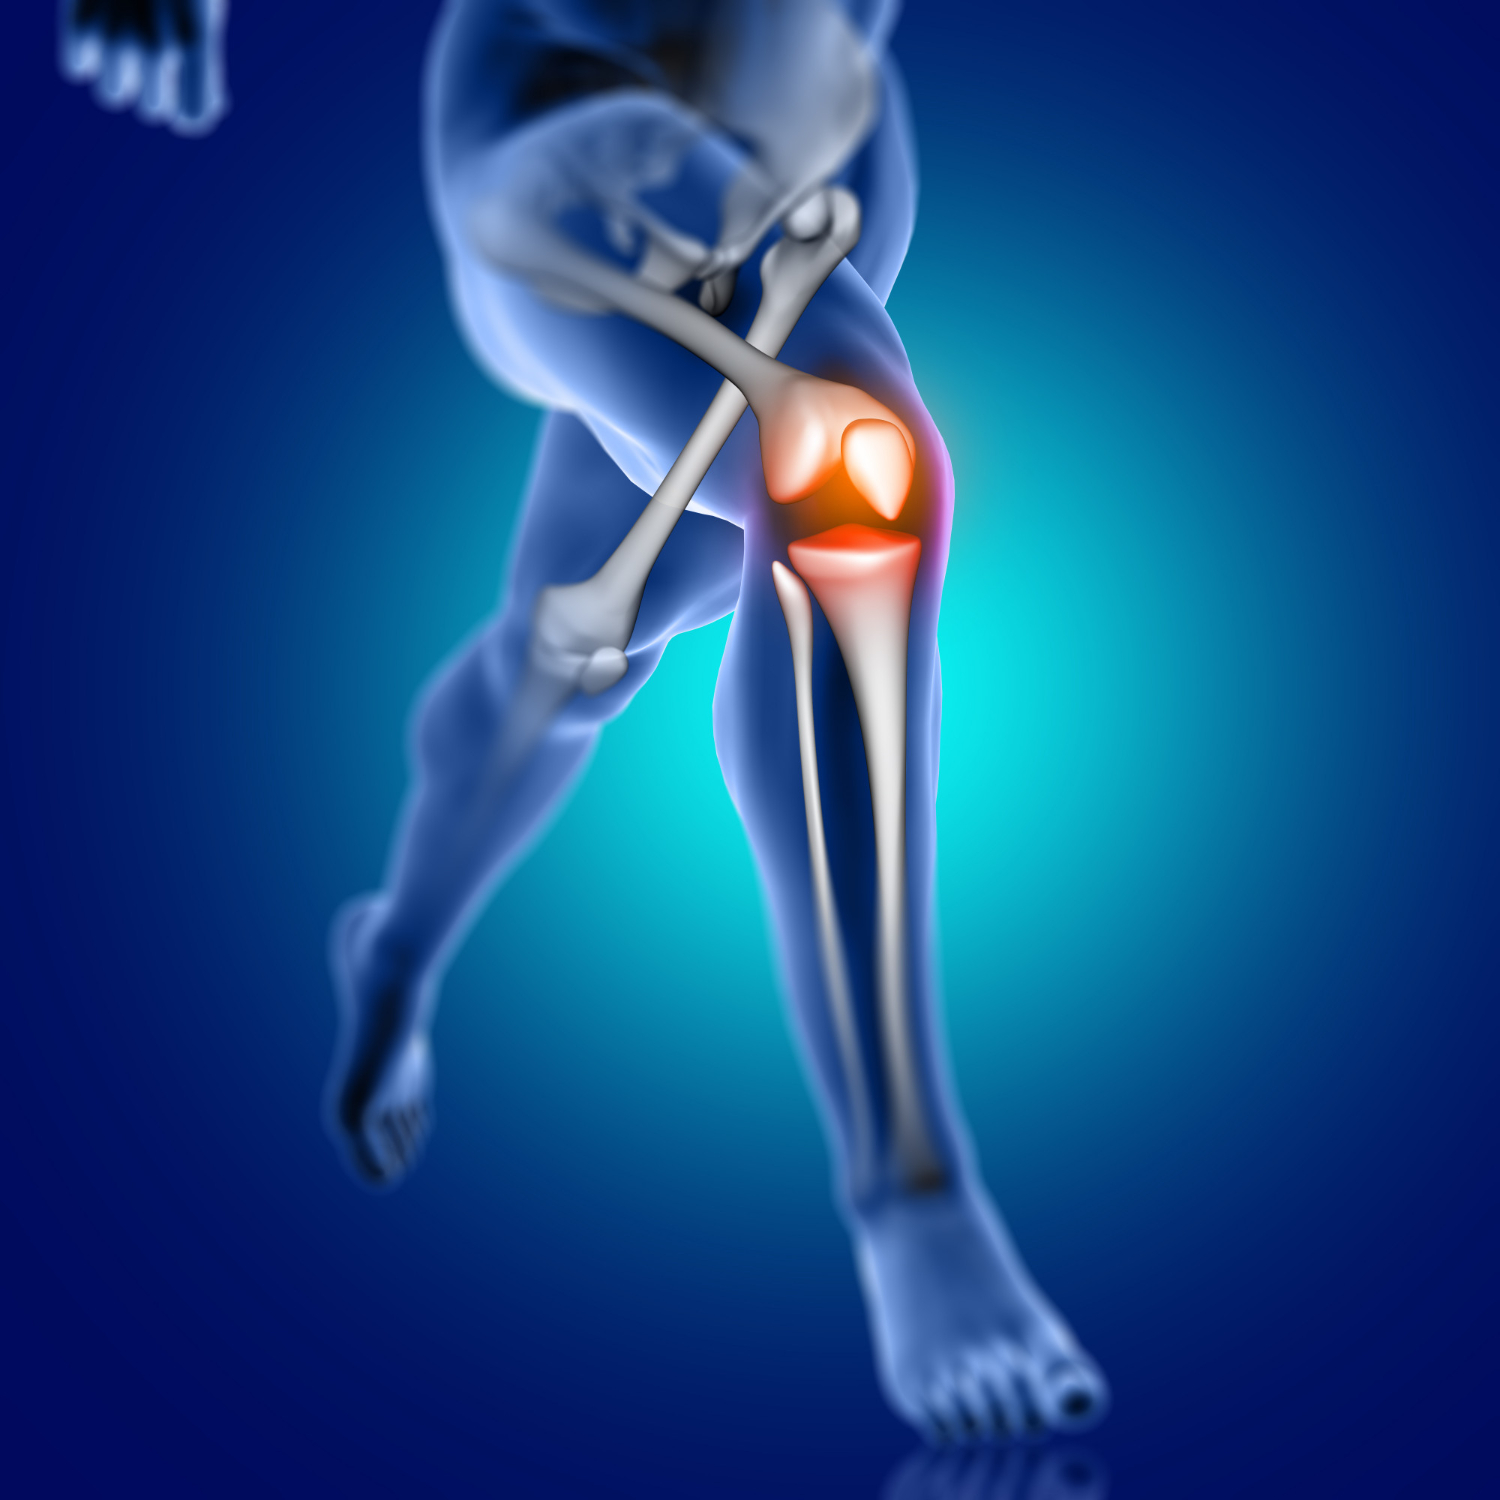

Lesões de joelho que são relacionadas ao futebol

O joelho é composto por cartilagem, ligamentos, fêmur, tíbia e patela, que são responsáveis pela função da articulação e do movimento. Por ser a maior articulação do corpo humano é constantemente submetida a grandes esforços e impactos, quando há algo de errado em alguma das partes, surgem dores – as quais podem ser classificadas como agudas ou crônicas.

“Das situações que colocam o joelho em risco, uma delas é o movimento de mudança de direção, do giro no futebol, é aquele em que o pé fica fixo no solo e o joelho gira, isso pode ocasionar traumas torcionais e lesão de ligamentos e meniscos. São complicações que podem ocorrer, não só no futebol, mas também em esportes que compartilham esses movimentos como o handebol, por exemplo”, destaca o Dr. Lucas.

Já as lesões ligamentares ou entorse, que são comuns entre os atletas, ocorrem quando há um rompimento dos ligamentos, sendo mais frequente no tornozelo e joelho, e o principal sintoma é a instabilidade, mas pode ocorrer também inchaço e dor.

O ortopedista explica que os sintomas das lesões após um trauma variam conforme a intensidade do trauma. Inchaço e dor são característicos do trauma e a lesão ligamentar provoca sensação de instabilidade, o joelho fica “frouxo”. “Quando rompido, o ligamento não se recupera, nesse caso é necessário que seja realizada uma cirurgia para restabelecer o joelho e a pessoa possa voltar a praticar atividades físicas”, frisa o Dr. Lucas.